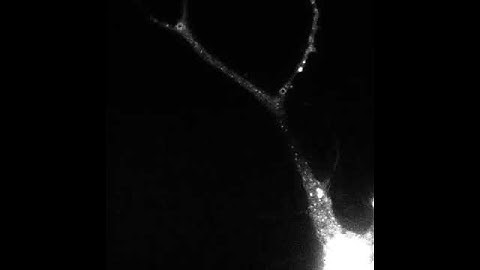

Yong Zhang, Visualizing AMPA receptors synaptic plasticity in vivo: McGovern Institute Symposium